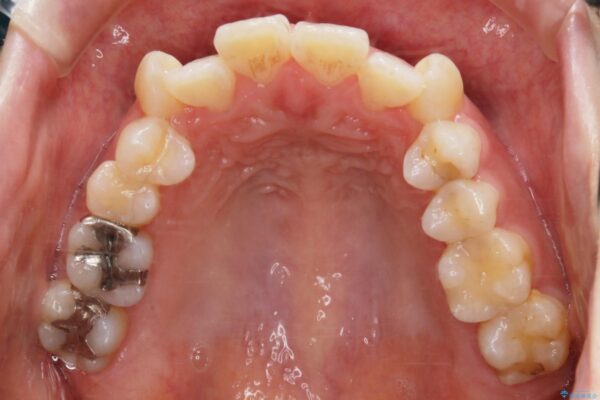

治療計画

お仕事柄、目立たない矯正装置をご希望されたため、今回はインビザラインと抜歯を組み合わせた治療で対応します。

抜歯後の大きなスペースの管理は通常ワイヤー矯正が得意ですが、こちらの患者様は奥歯の噛み合わせが比較的安定しており、犬歯の傾きを改善すれば良いため、マウスピースでも十分に精密な治療が可能と判断しました。

抜歯矯正

歯のガタつきの度合いが強い場合や、上下で大きく噛み合わせがズレている時などに、その改善のための大きなスペースを作る代表的手段が「抜歯」です。

一般的には第一小臼歯(犬歯の一つ隣の歯)を抜くことが多く、前歯のガタつきを改善したり口元を引っ込める場合に利用されます。